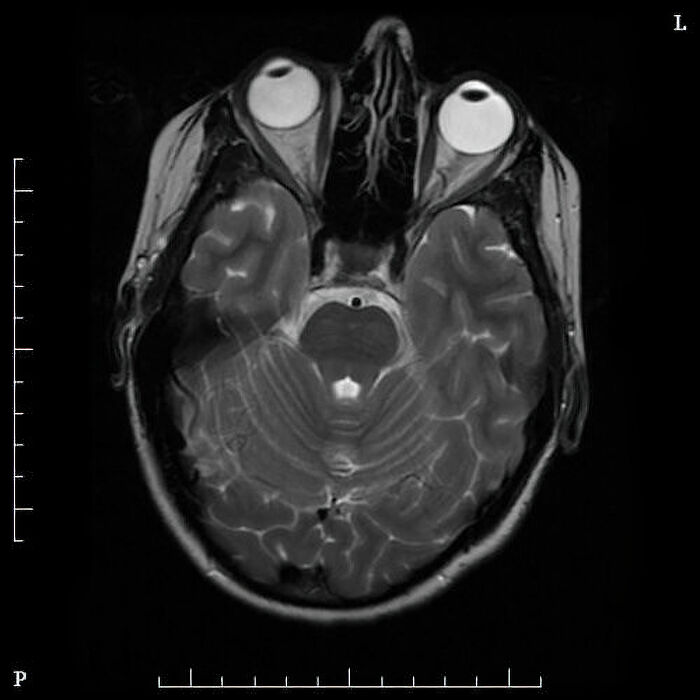

Sitis Inversus is a rare medical condition where your internal organs are entirely mirrored. It presents no issues whatsoever until trying to diagnose something. For example, the telltale sign of appendicitis is pain in the lower right. Someone with sitis Inversus will have their appendix in the lower right, which is usually how it’s discovered.

Image source: amanning072